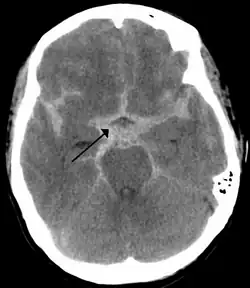

![]() CT-scanning, der viser en subaraknoidal blødning (det hvide område ved pilen) | |

En subaraknoidal blødning (undertiden blot kaldet ved akronymet SAH, af sub-arachnoidal hæmorragi) er en hjerneblødning i subaraknoidalrummet mellem den tynde hjernehinde (pia mater) og spindelhinden (arachnoidea mater), og altså ikke i selve hjernen. [1]